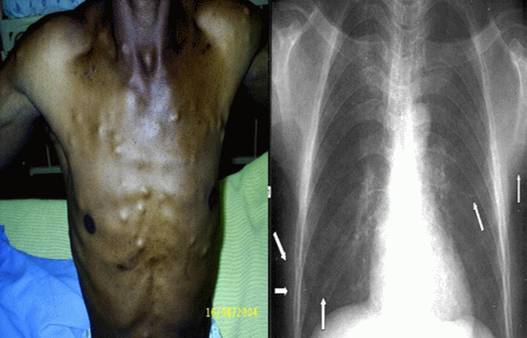

ATSL cũng có thể xảy ra tại các vị trí cách xa so với hệ thần kinh trung ương. Các đặc điểm lâm sàng tại mắt có thể tìm thấy trong khoang dưới võng mạc (subretinal space) hoặc thủy tinh thể và có thể đe dọa đến tầm nhìn hay thị lực do quá trình viêm hoặc các nang phá hủy, thoái hóa hoặc có thể dẫn đến bong võng mạc. Các nang kén cũng có thể dính và ký sinh trong cơ ngoài mắt. sinh ra chuyển động mắt bị giới hạn và có thể biểu hiện giống như liệt dây thần kinh sọ não. ATSL thể ở cơ xương hoặc mô dưới da có thể gây ra đau tại chỗ và các nốt kén đóng.

Sinh thiết não, da, hoặc cơ đưa ra các chẩn đoán xác định trong một bối cảnh hình ảnh lâm sàng có thể mơ hồ và tiến thoái lưỡng nan (otherwise ambiguous clinical situation) và có thể phương pháp chẩn đoán lựa chọn cho cơ mắt, hoặc đau cơ hoặc các nang dưới da. Sinh thiết các tổn thương ở xa so với hệ thần kinh trung ương cung cấp thêm các bằng chứng về bệnh ấu trùng sán lợn hệ thần kinh khi hình ảnh ở não không được chẩn đoán và sinh thiết não không thể thực hiện thoải mái và khả thi. Các xét nghiệm liên quan đến mắt sẽ rất nhạy để phát hiện các nang sán đóng kén trong mắt và rất cần thiết để chẩn đoán bất kỳ bệnh nhân nào nhằm loại trừ các vấn đề liên quan đến mắt. Tương tự như vậy, Chẩn đoán bất kỳ bệnh ATSL không phải thể thần kinh (nonneurologic cysticercosis), chẳng hạn như thể cơ, da,…thì cần đến điều tra bệnh sử, khám thực thể, chẩn đoán hình ảnh sẽ giúp loại trừ nguyên nhân và thể tại mắt.